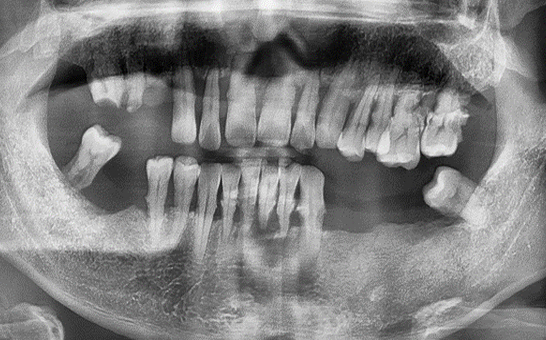

CASE 03 한** / 60대

전악임플란트

치료 시작 전 촬영 2022.05.15 | 치료 완료 후 촬영 2023.05.25

1 예후불량 치아 발치

2 발치 후 즉시 임플란트 식립 및 뼈이식

3 고정성 보철물로 수복 후 일상 회복